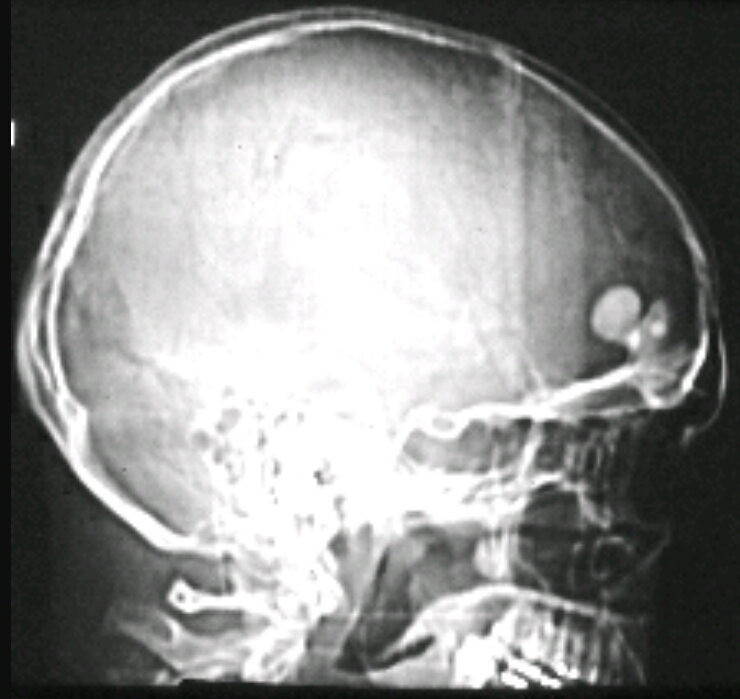

Patient is a 60 year old male has and has been complaining of pain, unexplained weight loss and recurrent respiratory infections. You take this xray and labs. Elevated ESR and M spike. What are the findings? Diagnosis?

Osteoporosis/osteopenia, soap bubble appearance

Multiple myeloma